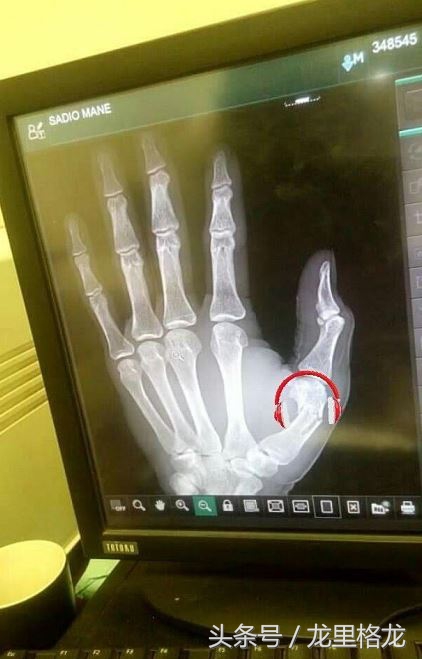

最牛逼的是,马内这周两场三球,是在手替国家队比赛时候骨折后完成的~也就是说骨折后他就休息了大概一周。。。就踢了两场比赛,进了三个球。。。所以说他成为利物浦第四位英超50球的球员,是多么让人钦佩的一件事情。去年我还记得大部分名宿都在吹萨拉赫可以去皇马巴萨之类的,今年都在吹马内去皇马巴萨了。可利物浦也不是球星加工厂啊。就好好留在利物浦吧~